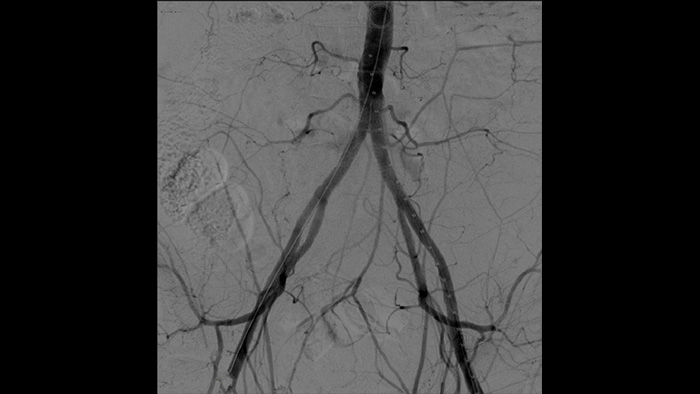

One of Spain’s leading specialists in minimally invasive vascular surgery is Dr. Ramon Vila, who is Head of the Angiology and Vascular Surgery Department, Bellvitge University Hospital, Barcelona, Spain. This hospital performs 1,000 vascular surgeries a year. With the Philips Zenition mobile C-arm, Dr. Vila is obtaining outstanding high-quality images that allow him to perform most vascular procedures at the low dose setting.

With the Zenition, our DSA image quality has improved greatly. We no longer see a grainy image. We just see a very clear image."

Dr. R. Vila, MD

Bellvitge University Hospital, Barcelona, Spain

Digital subtraction angiography (DSA) is used in interventional vascular procedures to clearly visualise blood vessels by removing structures that can obscure vessel visibility. Roadmap fluoroscopy overlays a previously acquired subtracted contrast image on the live fluoroscopy, allowing you to track a device without reinjecting contrast.